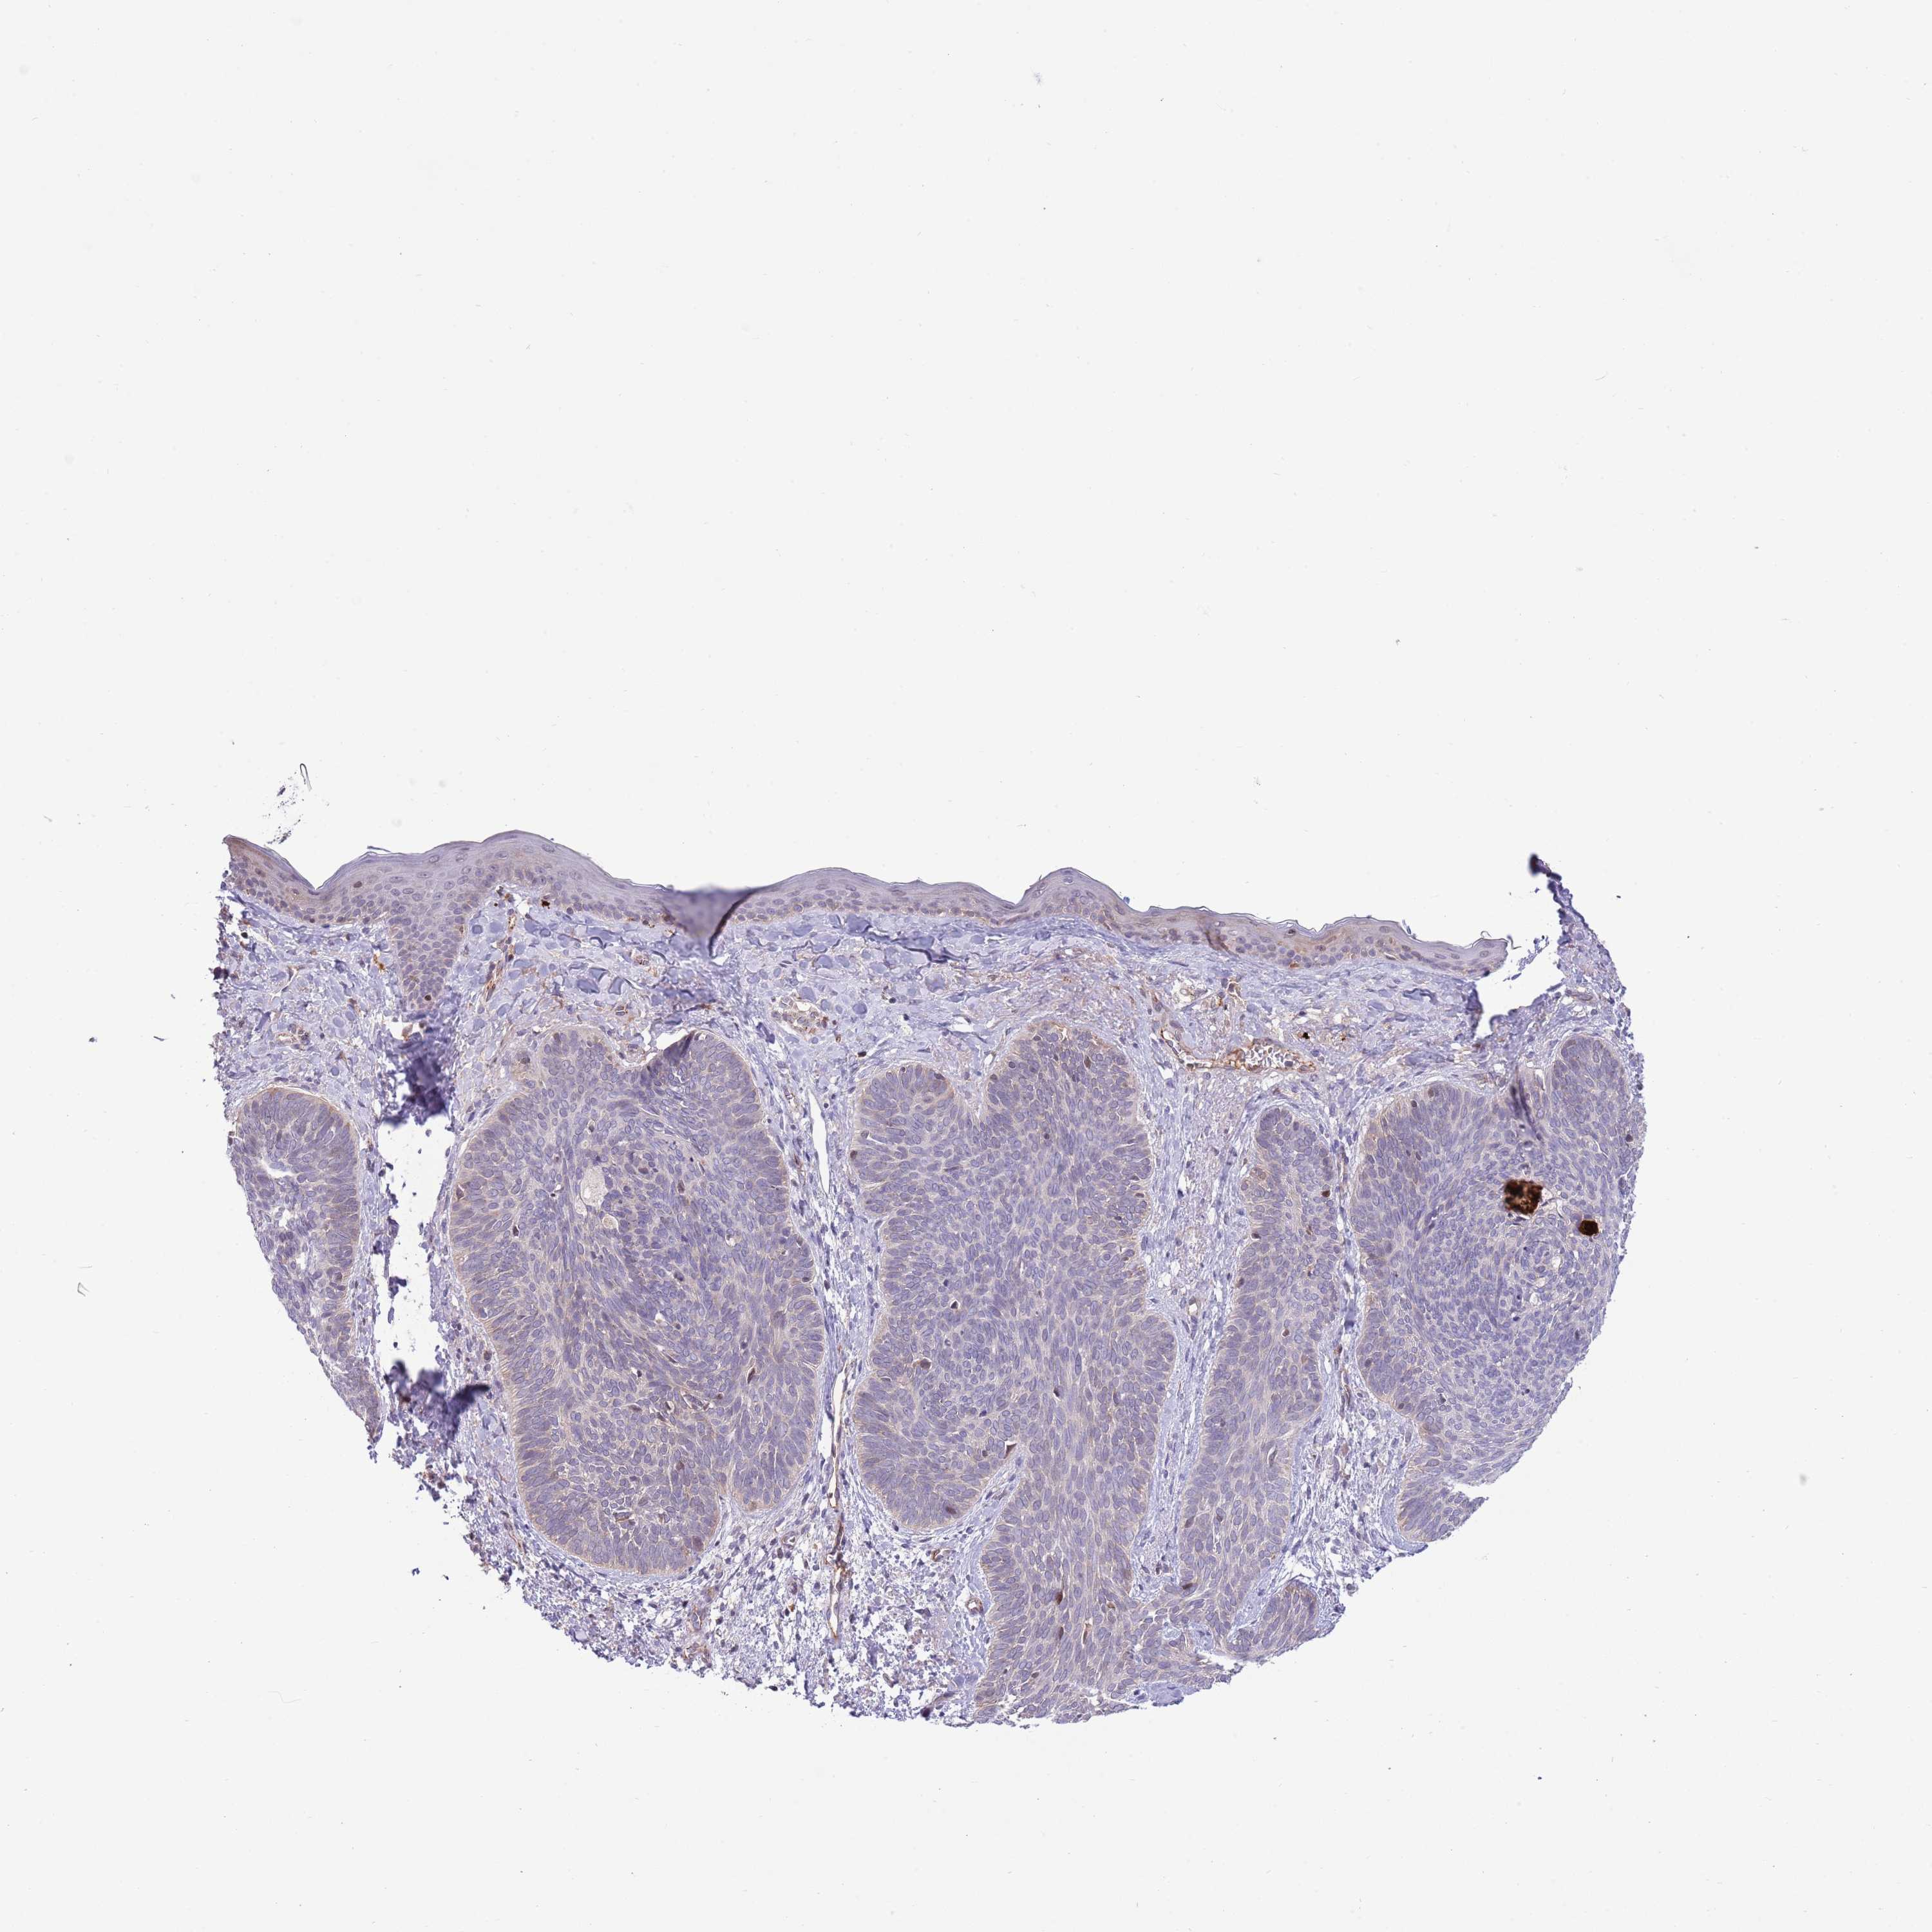

SKIN CANCER - Protein expressioni

A mouse-over function shows sample information and annotation data. Click on an image to view it in a full screen mode. Samples can be filtered based on level of antibody staining by selecting one or several of the following categories: high, medium, low and not detected. The assay and annotation is described here.

Antibody stainingi

Antibody staining in the annotated cell types in the current human tissue is reported as not detected, low, medium, or high, based on conventional immunohistochemistry profiling in selected tissues. This score is based on the combination of the staining intensity and fraction of stained cells.

Each image is clickable and will lead to virtual microscopy that enables deeper exploration of all samples and also displays staining intensity scores, fraction scores and subcellular localization as well as patient and tissue information for each sample.

Antibody HPA048767

Basal cell carcinoma